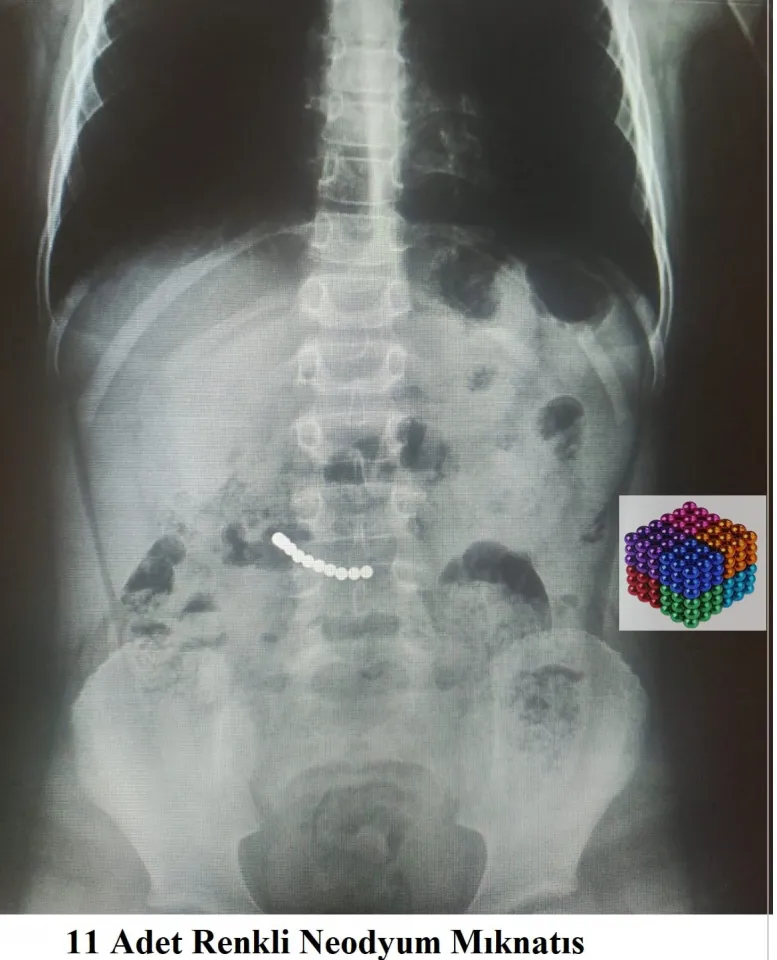

7 yaşındaki çocuğun midesinden 11 mıknatıs çıktı

Muğla'da bir çocuğun midesinden çıkan mıknatıslar doktorları şaşırttı.

Karın ağrısı şikayetiyle Muğla Eğitim ve Araştırma Hastanesine başvuran 7 yaşındaki U.K'nın kontrollerinde midesinde mıknatıs olduğu belirlendi.

Yaklaşık iki saat süren operasyonla çocuğun midesindeki 11 mıknatıs çıkarıldı.

Ekibiyle operasyonu gerçekleştiren hastanenin Çocuk Cerrahisi Ana Bilim Dalı Öğretim üyesi Prof. Dr. Süleyman Cüneyt Karakuş, bazı çocuklarda bu durumun ölümlere kadar giden sonuçlar doğurabileceğini belirterek, "Bazen küçük şeyler çocukların dikkatini çekebiliyor. Hastamızda mıknatısların midede yer değiştirmemesi, ameliyat kararı vermemizde etkili oldu." ifadesini kullandı.